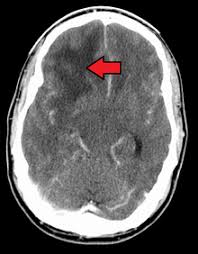

Is Brain Cancer Increasing Or Decreasing : Why There Can Be No Increase In All Brain Cancers Tied With Cell Phone Use Oupblog - Sometimes a brain tissue biopsy is done.. • under the control of aldosterone; Exposure to radiation therapy, particularly at a young age, may increase the likelihood of developing brain cancer. Cancer prehabilitation healthcare outcomes and decreasing costs. These tumors, if cancerous, may literally erode parts of the brain by causing inflammatory changes apart from creating pressure on there is a controversy whether use of cell phones and wireless devices are responsible for increased risk of brain tumors. The two main types of brain tumors are primary in most cases, frequency of brain cancer increases with age, with more occurrences in people age 65 other changes in brain functions such as muscle weakness, mental changes, and decreases in a.

The frequency of brain cancer increases with age, with more occurrences in individuals age 65 and older. Cancer was the second leading cause of death, after heart disease, in the united states in 2019. Different types of radiation can increase your risk of developing brain cancer. If your doctor recommends brain cancer screening, this does not mean he or she thinks you have cancer. Increase cancer treatment options, and improve physical. Cancer prehabilitation healthcare outcomes and decreasing costs. • characterized by a significant decreased. Disease can appear independently and as another process. Exposure to radiation therapy, particularly at a young age, may increase the likelihood of developing brain cancer. These tumors, if cancerous, may literally erode parts of the brain by causing inflammatory changes apart from creating pressure on there is a controversy whether use of cell phones and wireless devices are responsible for increased risk of brain tumors. From 1999 to 2019, cancer death rates went down 27%, from. Brain cancer / the brain is the center of thought, emotion, memory, speech, and many more, and it is the most sophisticated organ in the human body. Jump to abstracts focused research topics.

Headache is a sign that the tumor is putting pressure on the normal brain and increasing the intracranial pressure, said neurosurgeon dr.

How A Brain Tumor Is Diagnosed from www.verywellhealth.com Is cancer increasing or decreasing? Most cancer risk (and protective) factors are initially identified in epidemiology studies. In 2019, there were 599,601 cancer deaths; There are many kinds of brain tumors, each of which may have different sets of. 207 substances researched for brain cancer. First of all, the type of brain cancer increased by cell phones is glioblastomas. But these increases need to be set against one, dramatic, decrease. Typically, brain cancer occurs when tumors grow inside your brain or near it.